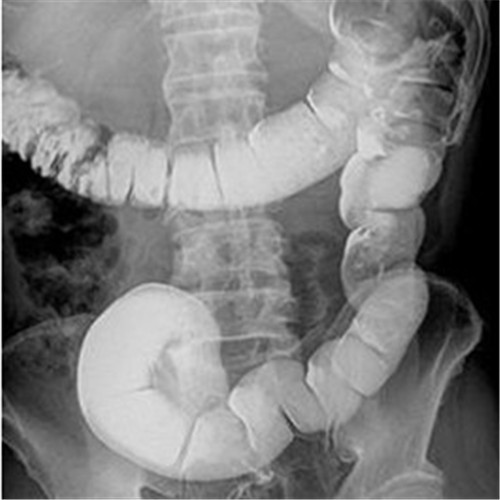

潰瘍性結腸炎影像檢查